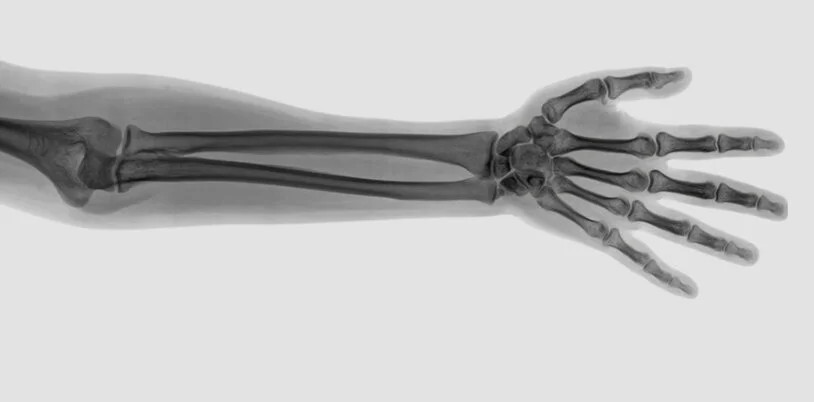

Elbow Conditions

Elbow conditions can be extremely debilitating…but you don’t have to suffer

Elbow Fractures

Elbow Fractures.